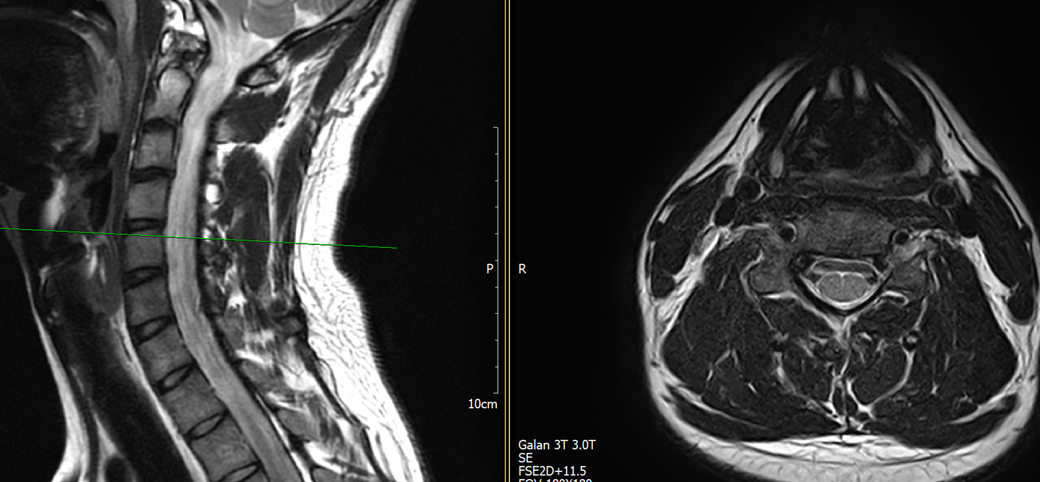

목과 오른쪽 어께 통증이 있어 mri를 찍어왔는데, 사진에서 의심되는 부분 있을까요?

통증은 10년 정도 되었고, 통증 의학과 가서 신경차단술 2회 받은 상태입니다.

토요일에 mri 찍고 주말이라 물어볼 곳이 없어 먼저 여기에 사진 올려봅니다. 답변 부탁드립니다.

MRI만 보면 굉장히 깨끗한 목입니다.

디스크탈출은 없고 신경뿌리가 압박될만한 모습도 전혀 보이지 않습니다.

통증 의학과에서는 아마 MRI 없이 증상을 기반으로 신경차단술을 하셨을거라 생각됩니다.

지금은 MRI에서 잘 보이지 않는 디스크내장증일 가능성이 높아보이며 경추전만 자세를 잘 유지해주시는게 가장 큰 도움이 되겟습니다.